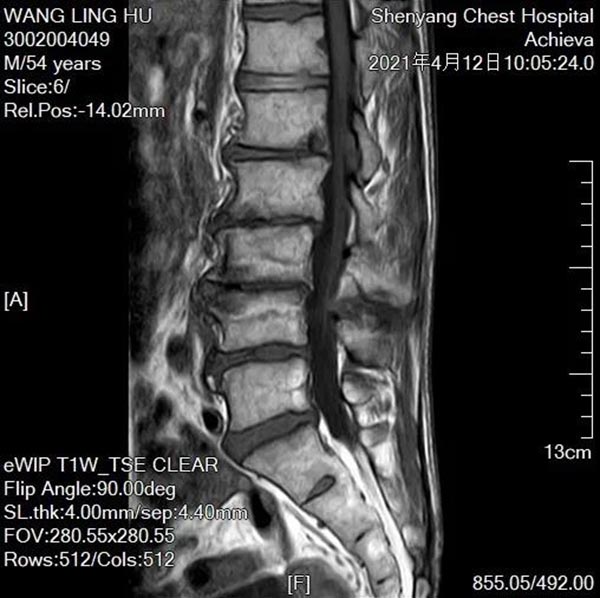

55岁的老王被腰腿痛麻困扰了近十年。十年来四处求医,病情却未得到缓解,反而越来越重。9个月前老王自己感觉疼痛已经无法忍受,下地行走困难,夜不能能昧,病情加剧生活都无法自理。最后来到沈阳市第十人民医院骨一科找到柳盛春主任,陆续完善脊柱全长正侧位,颈胸腰椎磁共振等检查后,柳主任发现患者神经根性症状及浅感觉减退范围同腰椎轴性痛等体征混杂在一起,与影像学资料不符,这给诊断带来了巨大的困难。经反复的病情研究,细致的查体,最后柳主任认为老王得的是退变性腰椎侧凸。

OLIF融合器及椎弓根螺钉置入后影像